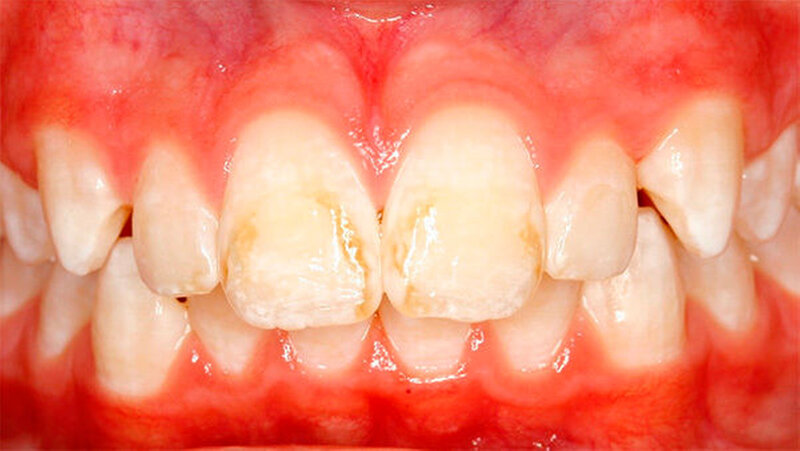

Das klinische Bild der MIH reicht von einem bis zu vier betroffenen Molaren, nur selten sind alle Zähne in ähnlicher Ausprägung geschädigt [Weerheijm et al., 2001]. Die bleibenden Frontzähne können ebenfalls betroffen sein, diese weisen allerdings in der Regel keinen Schmelzeinbruch auf und sind selten bis gar nicht überempfindlich [Weerheijm et al., 2001] (Abbildung 2).

Bisher wurde nicht beschrieben, dass die Frontzähne nur allein betroffen sein könnten. Meist wird - wenn die Frontzähne zusätzlich zu den Molaren betroffen sind - über mangelnde Ästhetik geklagt und die Kinder aufgrund ihres Aussehens gehänselt.

In schwerwiegenden Fällen kann der Einsatz eines Komposits das beste Ergebnis erzielen (Abbildungen 2, 13 und 14)